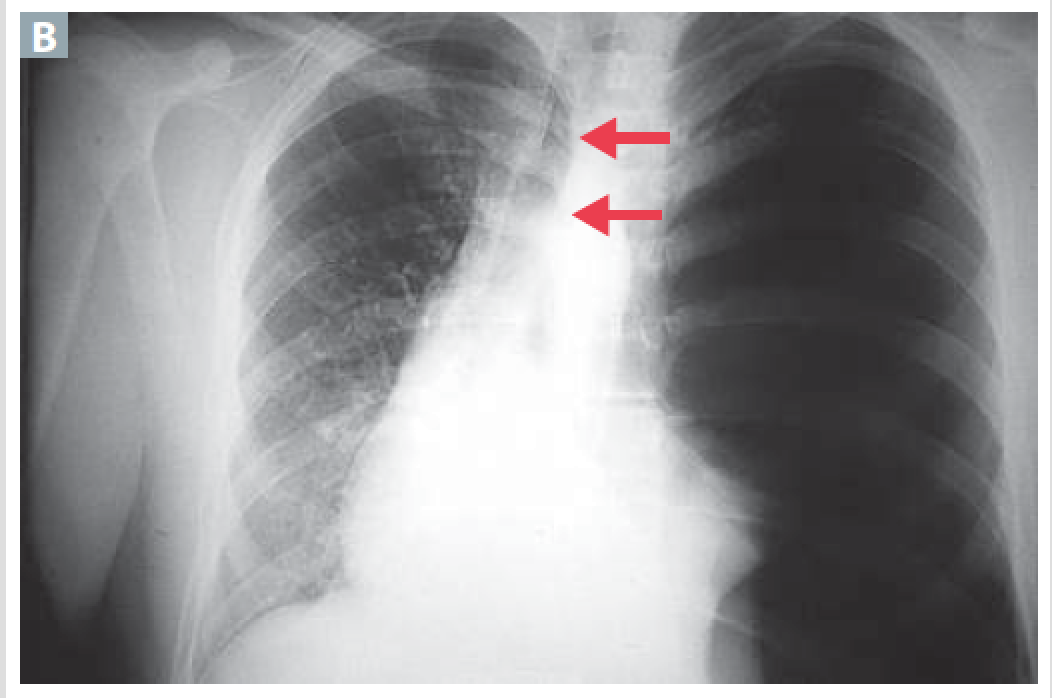

Accumulation of air in pleural space. Presenting with dyspnea, uneven chest expansion. Chest pain decrease tactile fremitus, hyperresonance and diminished breath sound.

Pneumothrax

Physical findings in simple pneumothorax

Decrease breath sounds, Hyperresonant, decrease fremitus